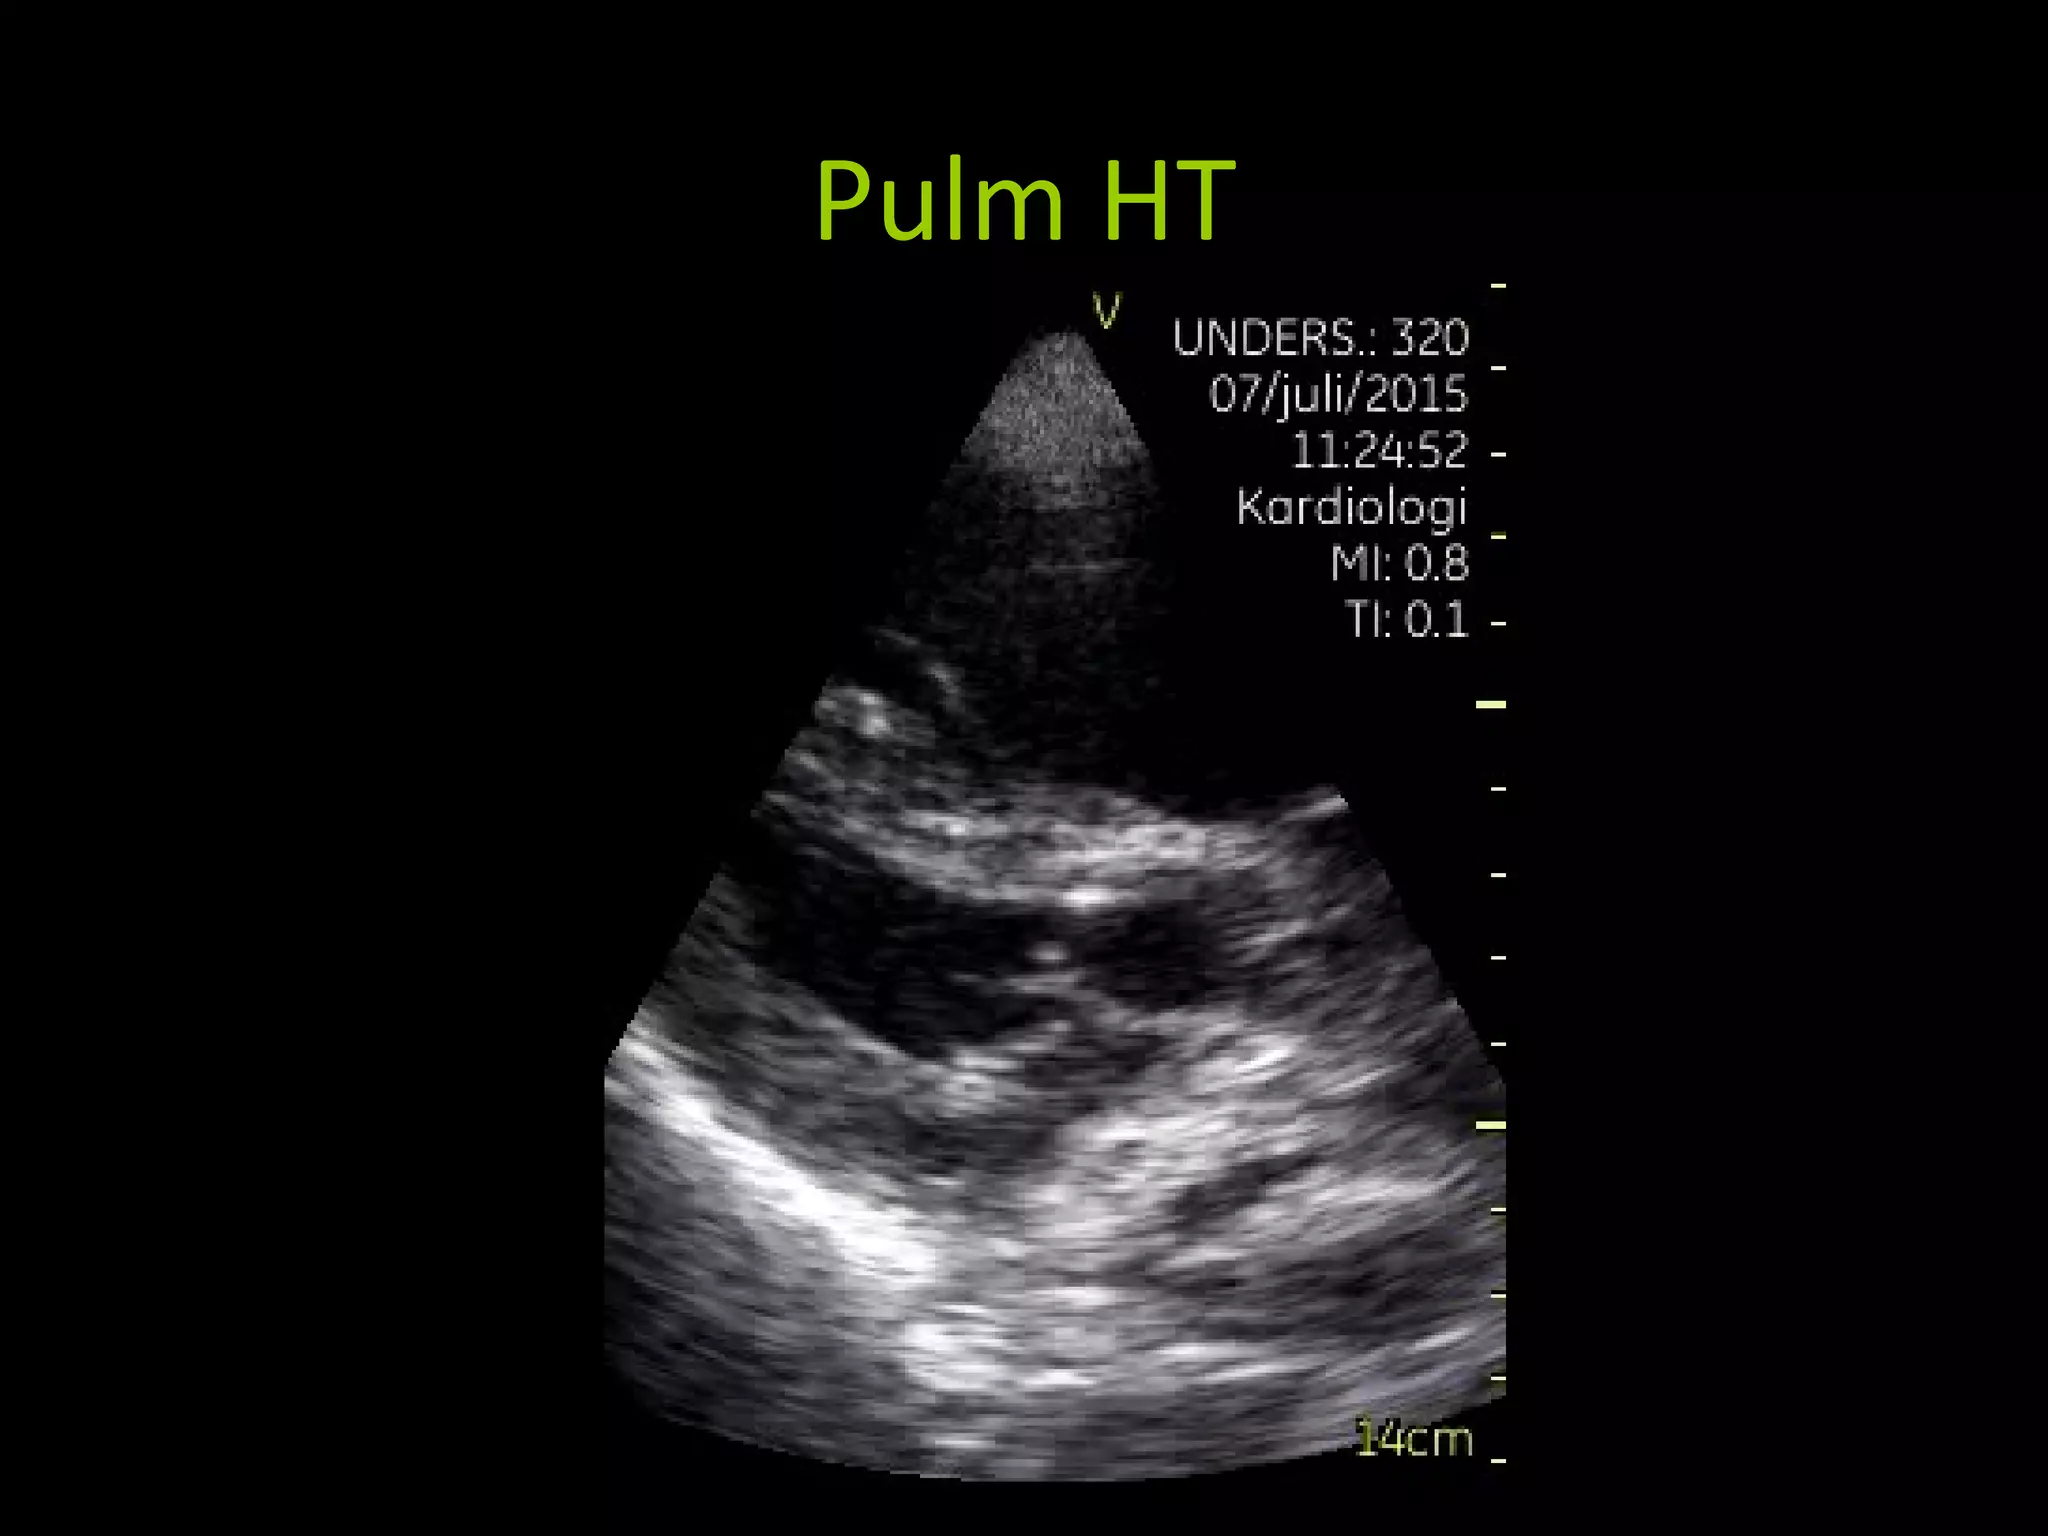

PULM HT

High ventilator settings